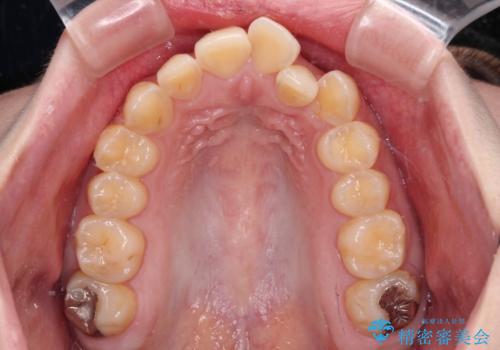

- 前歯のデコボコとクロスバイトが気になり、インビザラインによる矯正治療を希望して来院された患者様です。

上顎側切歯(上の真ん中から2番目の歯)が舌側転位している場合、無理して動かそうとすると歯髄壊死を起こすリスクが高い印象があります。

インビザライン単体でも治療は可能ですが、安全策としてインビザラインで歯列を移動する前に上顎前歯をワイヤー矯正で整え、その後上下歯列をインビザラインにて矯正治療を行うこととしました。

舌側転位している側切歯特有の、切縁の位置が不揃いであったり、根元が内側に引っ込んだ状態であったりという、インビザライン独特の仕上がりになることなく、きれいに整った歯列とすることができました。